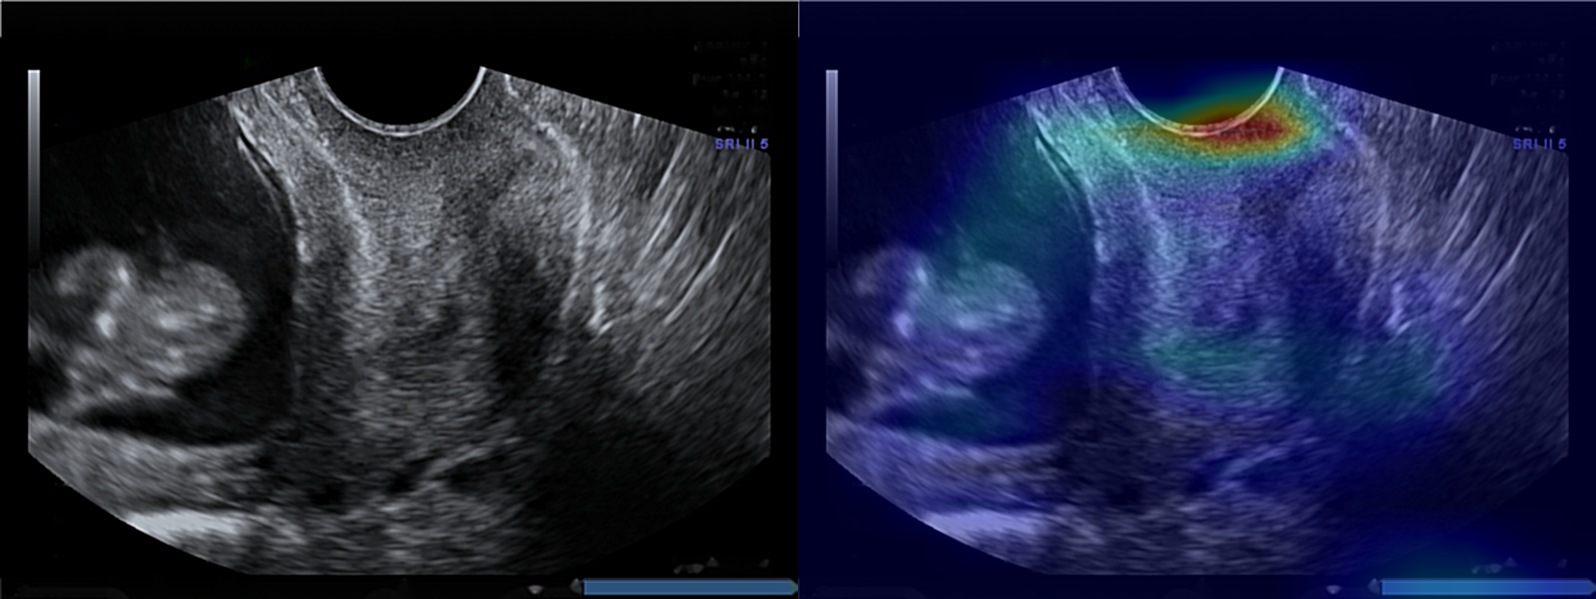

3.3 Grad-CAM

It was found by Baños et al. [14] that information extracted from the region along the length of the anterior cervical stroma is relevant to control vs preterm classification. In addition, Pachtman et al. [15] proved that the region along the length of the anterior cervical stroma and the analysis of its relative organization of cervical collagen fibers may have the capacity to identify preterm birth. To the contrary, Grad-CAM shows the preterm class is classified based on the lower segment of the cervix, close to the ectocervix. We can note that during classification, the neural network focuses on the heterogeneity of the density of tissues around the cervix. For the control class, our model is focusing on the top part of the largest homogeneous region in middle part of anterior cervical lip, which is the part of the cervix closest to the transducer. Examples of Grad-CAM results can be seen in Figure 5 for the preterm and control class.